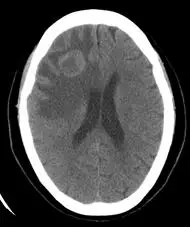

本圖為非增強腦部電腦斷層(non-contrast CT, NCCT)軸切面。影像可見右側大腦半球白質(white matter)呈現較大範圍低密度(hypodensity)改變,此為血管源性水腫(vasogenic edema)的典型 CT 表現——水腫沿白質纖維束擴散,皮質相對保留(手指狀分布)。中線結構無顯著偏移,腦室系統形態尚可辨認。

此 NCCT 所見提供了「有病灶、有水腫」的線索,但無法區分:

- 腦轉移瘤(metastasis)

- 高惡度膠質瘤(glioblastoma)

- 腦膿瘍(brain abscess)

- 脫髓鞘疾病(demyelinating disease)

因此需進一步做含碘對比劑增強 CT,觀察是否出現環形強化(ring enhancement)或均勻強化,以縮小鑑別診斷範圍。